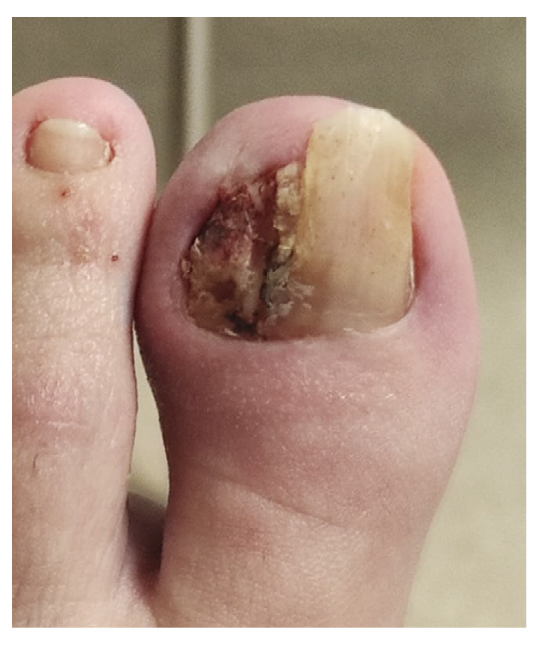

La paciente refiere proceso de inicial de onicocriptosis de 7 meses de evolución (septiembre de 2022), en el borde medial del primer dedo del pie izquierdo, con la presencia de tejido de granulación ungueal en dicho borde, el cual le produce dolor e inflamación digital (Figura 1). La paciente recibe tratamiento por su podólogo que consiste en quiropodia y limpieza del canal; se pautan posteriormente curas diarias con mupirocina para la lesión. Existe mala evolución de la lesión en los días siguientes con aumento de dolor y sensibilidad al tacto. Se modifica el tratamiento pautando amoxicilina/ácido clavulánico 875/125 mg, 1/8 h junto con el uso de analgésicos orales (Figura 2). La paciente continúa con mala evolución sintomatológica y acude a su centro de salud donde se realiza radiografía con la cual se descarta la presencia de infección profunda (osteomielitis).

Figura 2. Progresión clínica tras tratamiento ATB y analgésico.

Tras empeoramiento del cuadro clínico, el 14 de noviembre de 2022 se realiza en su centro de salud la retirada parcial de la placa ungueal lateral del pie izquierdo junto con raspado, retirando tejido hiperqueratósico y de granulación. El procedimiento es repetido 48 h más tarde (16 de noviembre de 2022) por no haber retirado toda la lesión (Figura 3), cambiando el tratamiento antibiótico a anaclosil 500 mg 1/6 h y posteriormente a ciprofloxacino 500 mg 1/12 h durante las siguientes semanas.

Figura 3. Semana 8. Resección parcial de tejido hiperplásico realizado en su centro de salud.